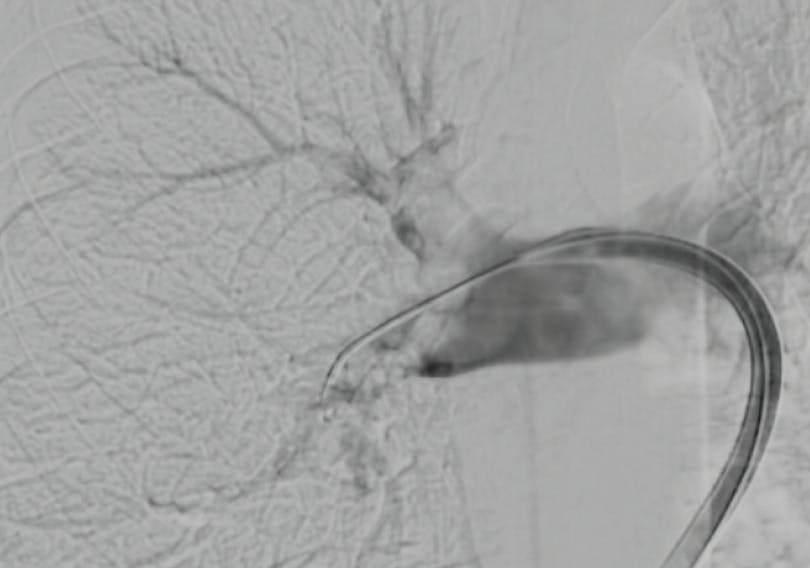

The in-line blood return system allowed real-time visualization of aspirated thrombus (Figure 3) and delivered negligible blood loss. Total contrast volume was approximately 50 mL. Completion angiography showed near-complete restoration of bilateral perfusion (Figure 4). Postprocedure PA pressures were 21/11 mm Hg. Total device time was 22 minutes with no arrhythmia, vascular injury, or hemodynamic instability.

Figure 4. Visible thrombus retrieval with a closed-loop aspiration and reinfusion system. AVENTUS Clot Filter demonstrating collected thrombus segments readily visible during aspiration. This visual feedback confirms device effectiveness in real time and allows immediate assessment of clot burden removed (A). Organized display of extracted thrombus from the right (left side of image) and left (right side of image) PA systems, demonstrating removal of large, centrally located embolic casts consistent with the patient’s angiographic findings (B).